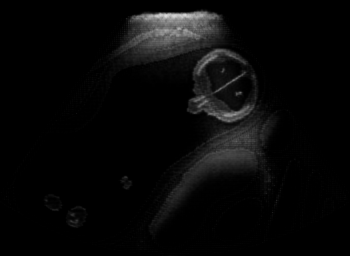

Real in-vivo images. 22 ultrasound sequences were collected using a GE Voluson E8 machine during standard fetal screening exams of 8 patients. Each sequence is several seconds long. We extracted all 4427 frames and resize them to , see Fig. 2 for some examples. The resulting image set was randomly split into training-validation-test sets by a 80-10-10% ratio.